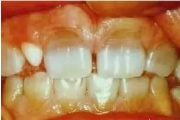

Fluoroos

Fluoroosi